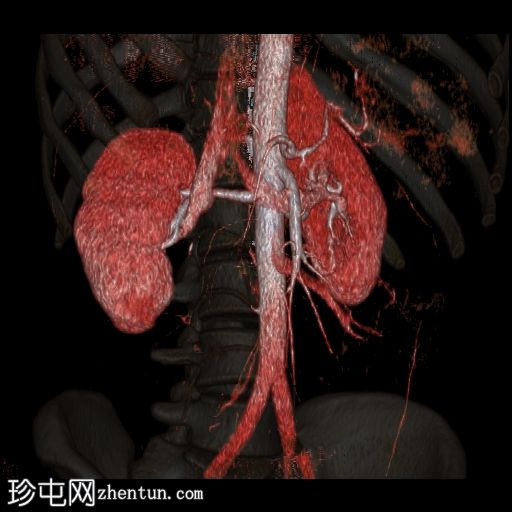

容积渲染

15.jpg

透明度

CT肾血管造影显示一条起源于左肾下段的副肾静脉,该静脉环绕主动脉走行,并接受来自腰静脉的属支,走行于主动脉后方,最终汇入下腔静脉。

本病例展示了一条环绕主动脉的副左肾静脉,其走行于主动脉后方并汇入下腔静脉,而右肾静脉解剖结构正常。

双侧肾动脉解剖结构正常,双侧肾动脉均起源于L2椎体水平的腹主动脉,管径正常,无狭窄、动脉瘤、夹层或副动脉。

双侧重复肾盂输尿管系统,上下极部分明显。右侧重复的输尿管在中段汇合,而左侧输尿管在进入膀胱前仍部分分离,符合双侧部分输尿管重复畸形(双分输尿管)。双肾大小、位置、轮廓和实质厚度均正常,造影剂浓度和排泄功能正常。未见肾结石、肾积水或局灶性肾脏病变。